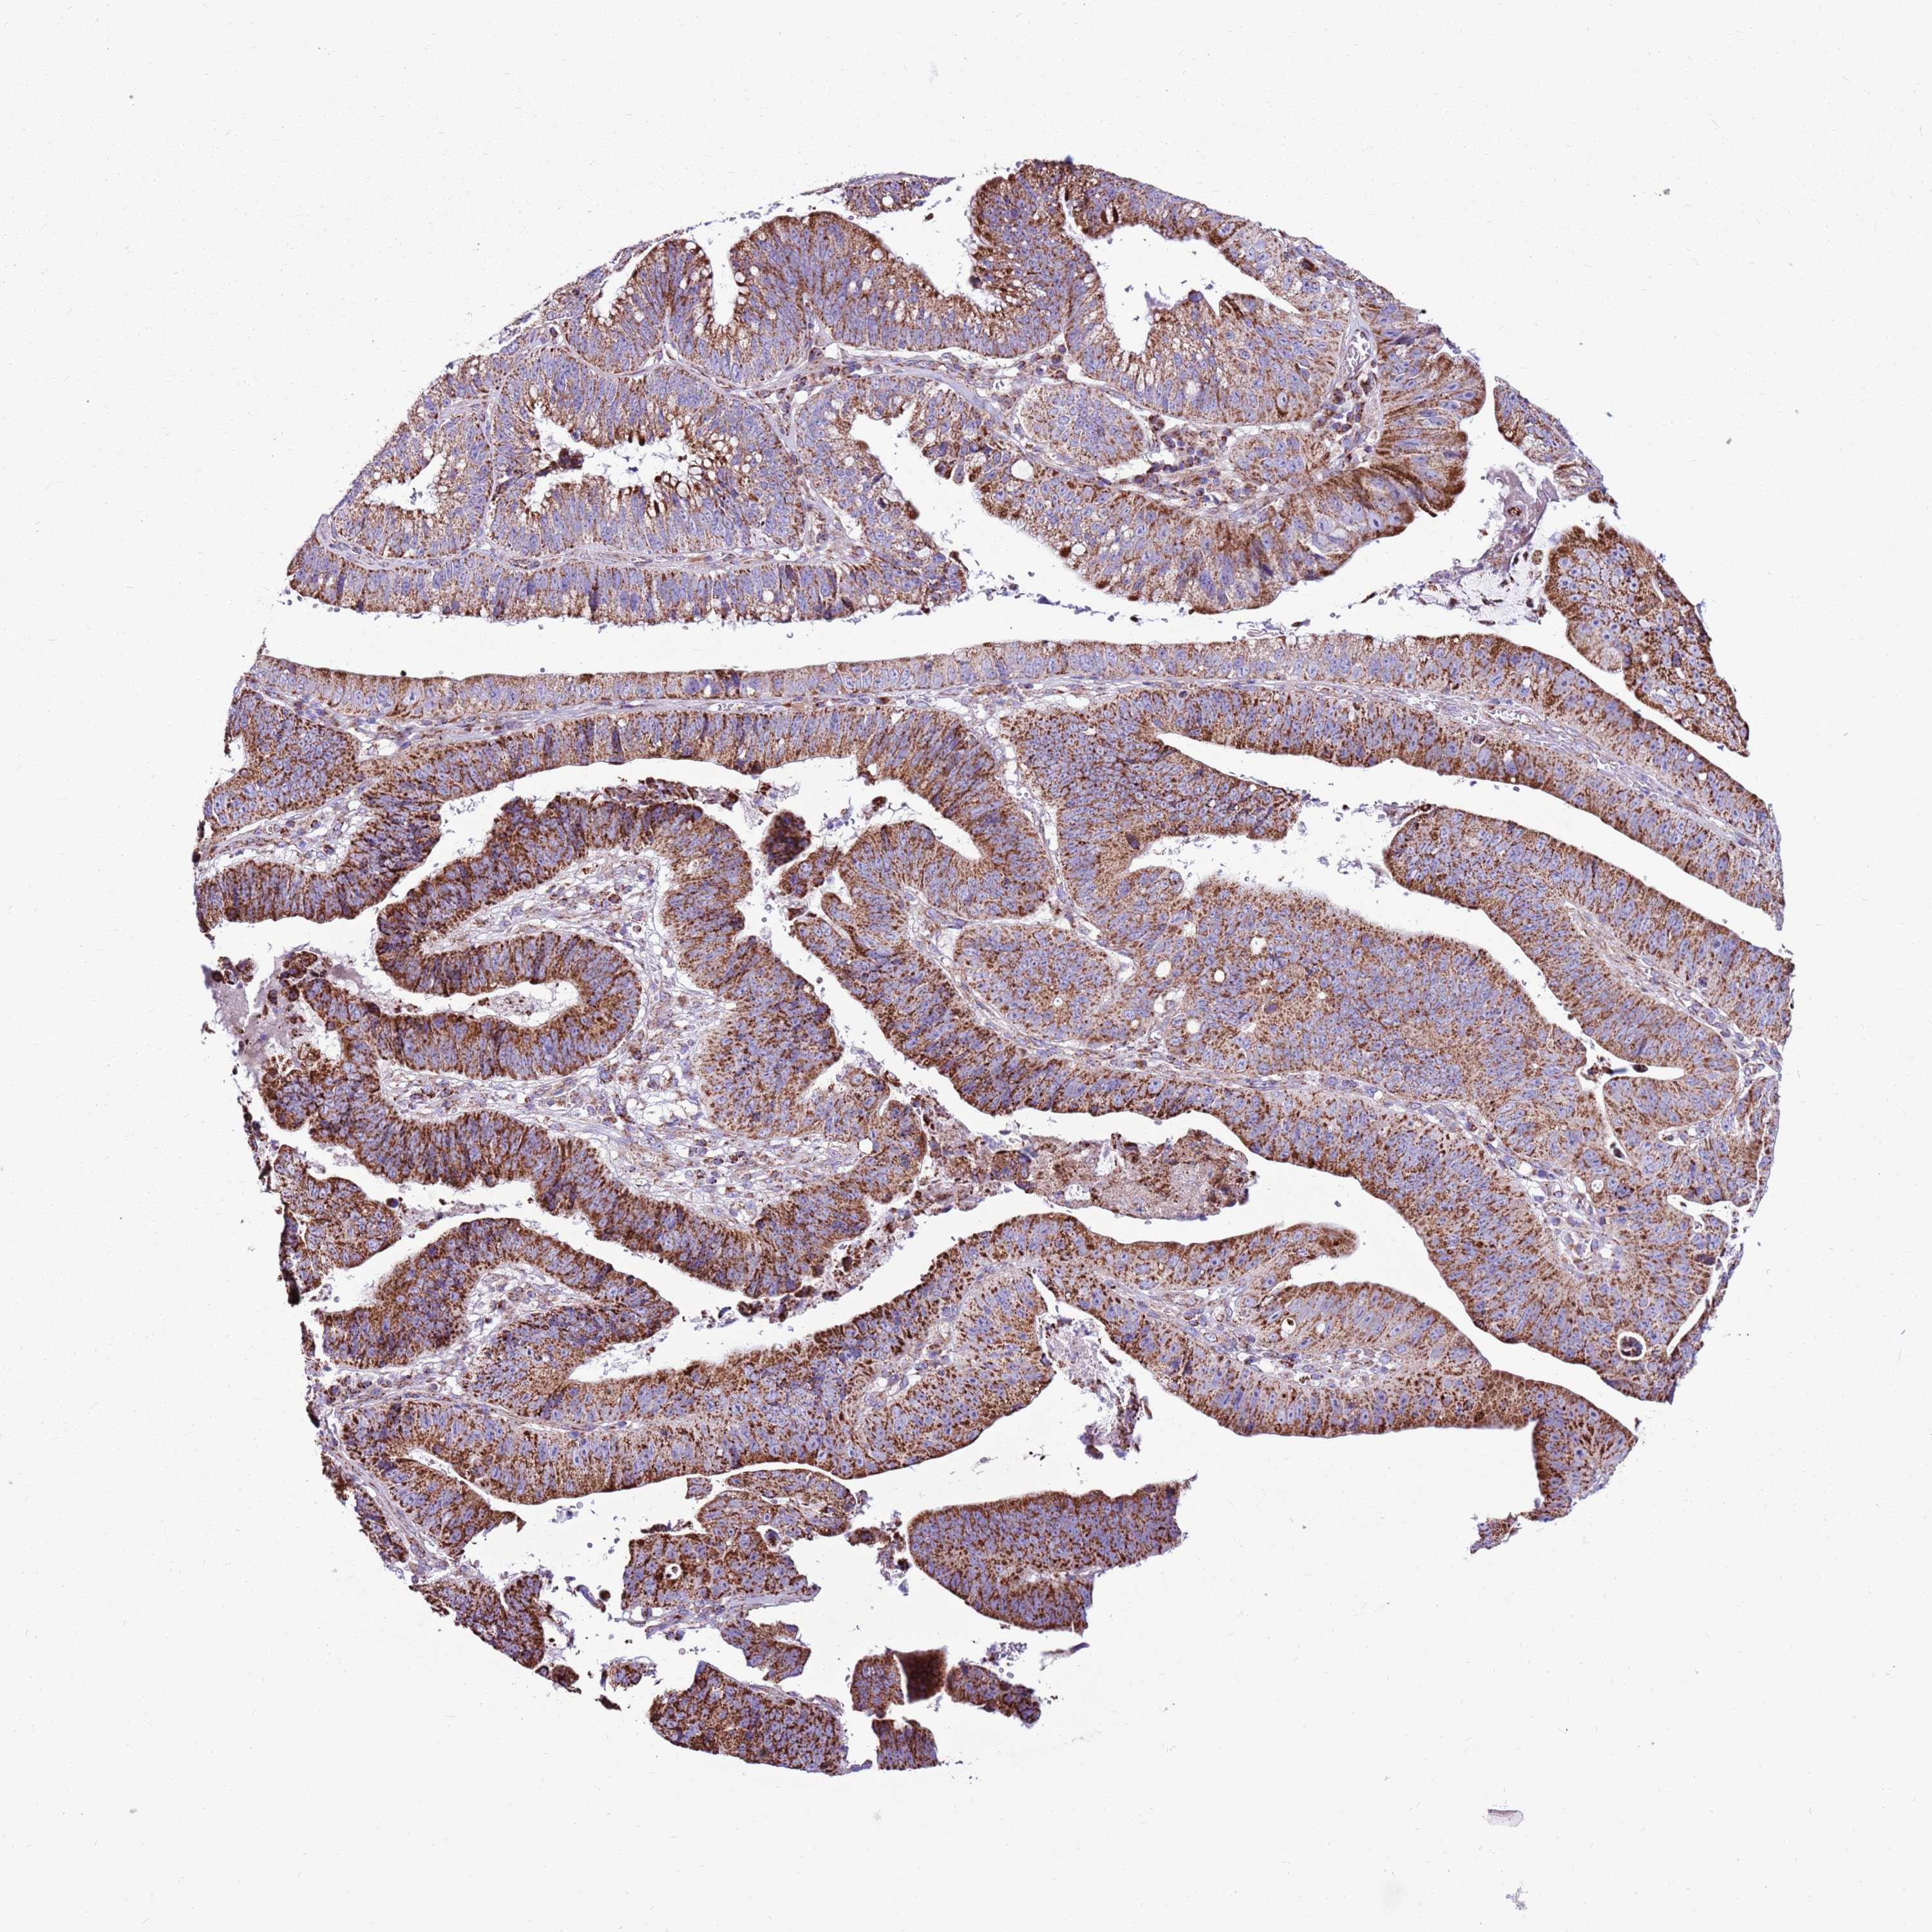

STOMACH CANCER - Protein expressioni

A mouse-over function shows sample information and annotation data. Click on an image to view it in a full screen mode. Samples can be filtered based on level of antibody staining by selecting one or several of the following categories: high, medium, low and not detected. The assay and annotation is described here.

Note that samples used for immunohistochemistry by the Human Protein Atlas do not correspond to samples in the TCGA dataset.

Antibody stainingi

Antibody staining in the annotated cell types in the current human tissue is reported as not detected, low, medium, or high, based on conventional immunohistochemistry profiling in selected tissues. This score is based on the combination of the staining intensity and fraction of stained cells.

Each image is clickable and will lead to virtual microscopy that enables deeper exploration of all samples and also displays staining intensity scores, fraction scores and subcellular localization as well as patient and tissue information for each sample.

Antibody HPA041062

Antibody HPA045473

Staining

High

Medium

Low

Not detected

Intensity

Strong

Moderate

Weak

Negative

Quantity

>75%

75%-25%

<25%

None

Location

Nuclear

Cytoplasmic/membranous

Cytoplasmic/membranous,nuclear

Adenocarcinoma, NOS